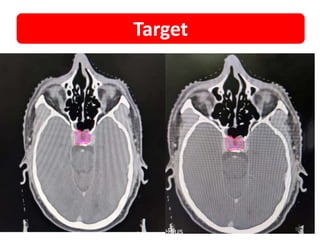

Target

99

• NAME • UMR •PRESENTATION • Vomiting, Head reeling sensation, Involuntary movements of all limbs • MRI 1. 2.3 × 1.6 × 1.6 cm, Dumbbell shaped lesion in sellar region 2. Extending into Suprasellar location 3. Pituitary gland not separated from lesion 4. Optic chiasm – compressed & superiorly displaced 5. Doubtful B/L Parasellar extension (R>L) with encasement of cavernous segment B/L ICA (R>L) • SURGERY • Endoscopic Trans sphenoid Excision and Near total excision • BIOPSY • F/S/O Pituitary Macro adenoma • SRS • FSRT – 25Gy / 5# • IHC • Synaptophysin +VE , • Chromogranin +VE Case details 98

• 99.

• 100.